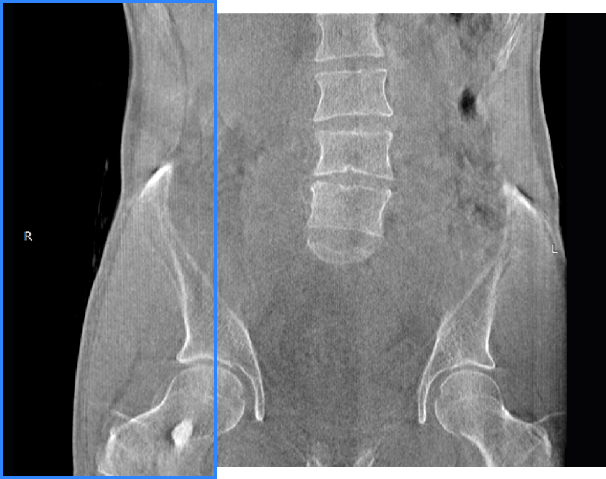

• 髖關節

支持雙腿或雙側髖關節掃描 | 方便對比,降低漏診誤診

FOV 250mm

FOV 350mm